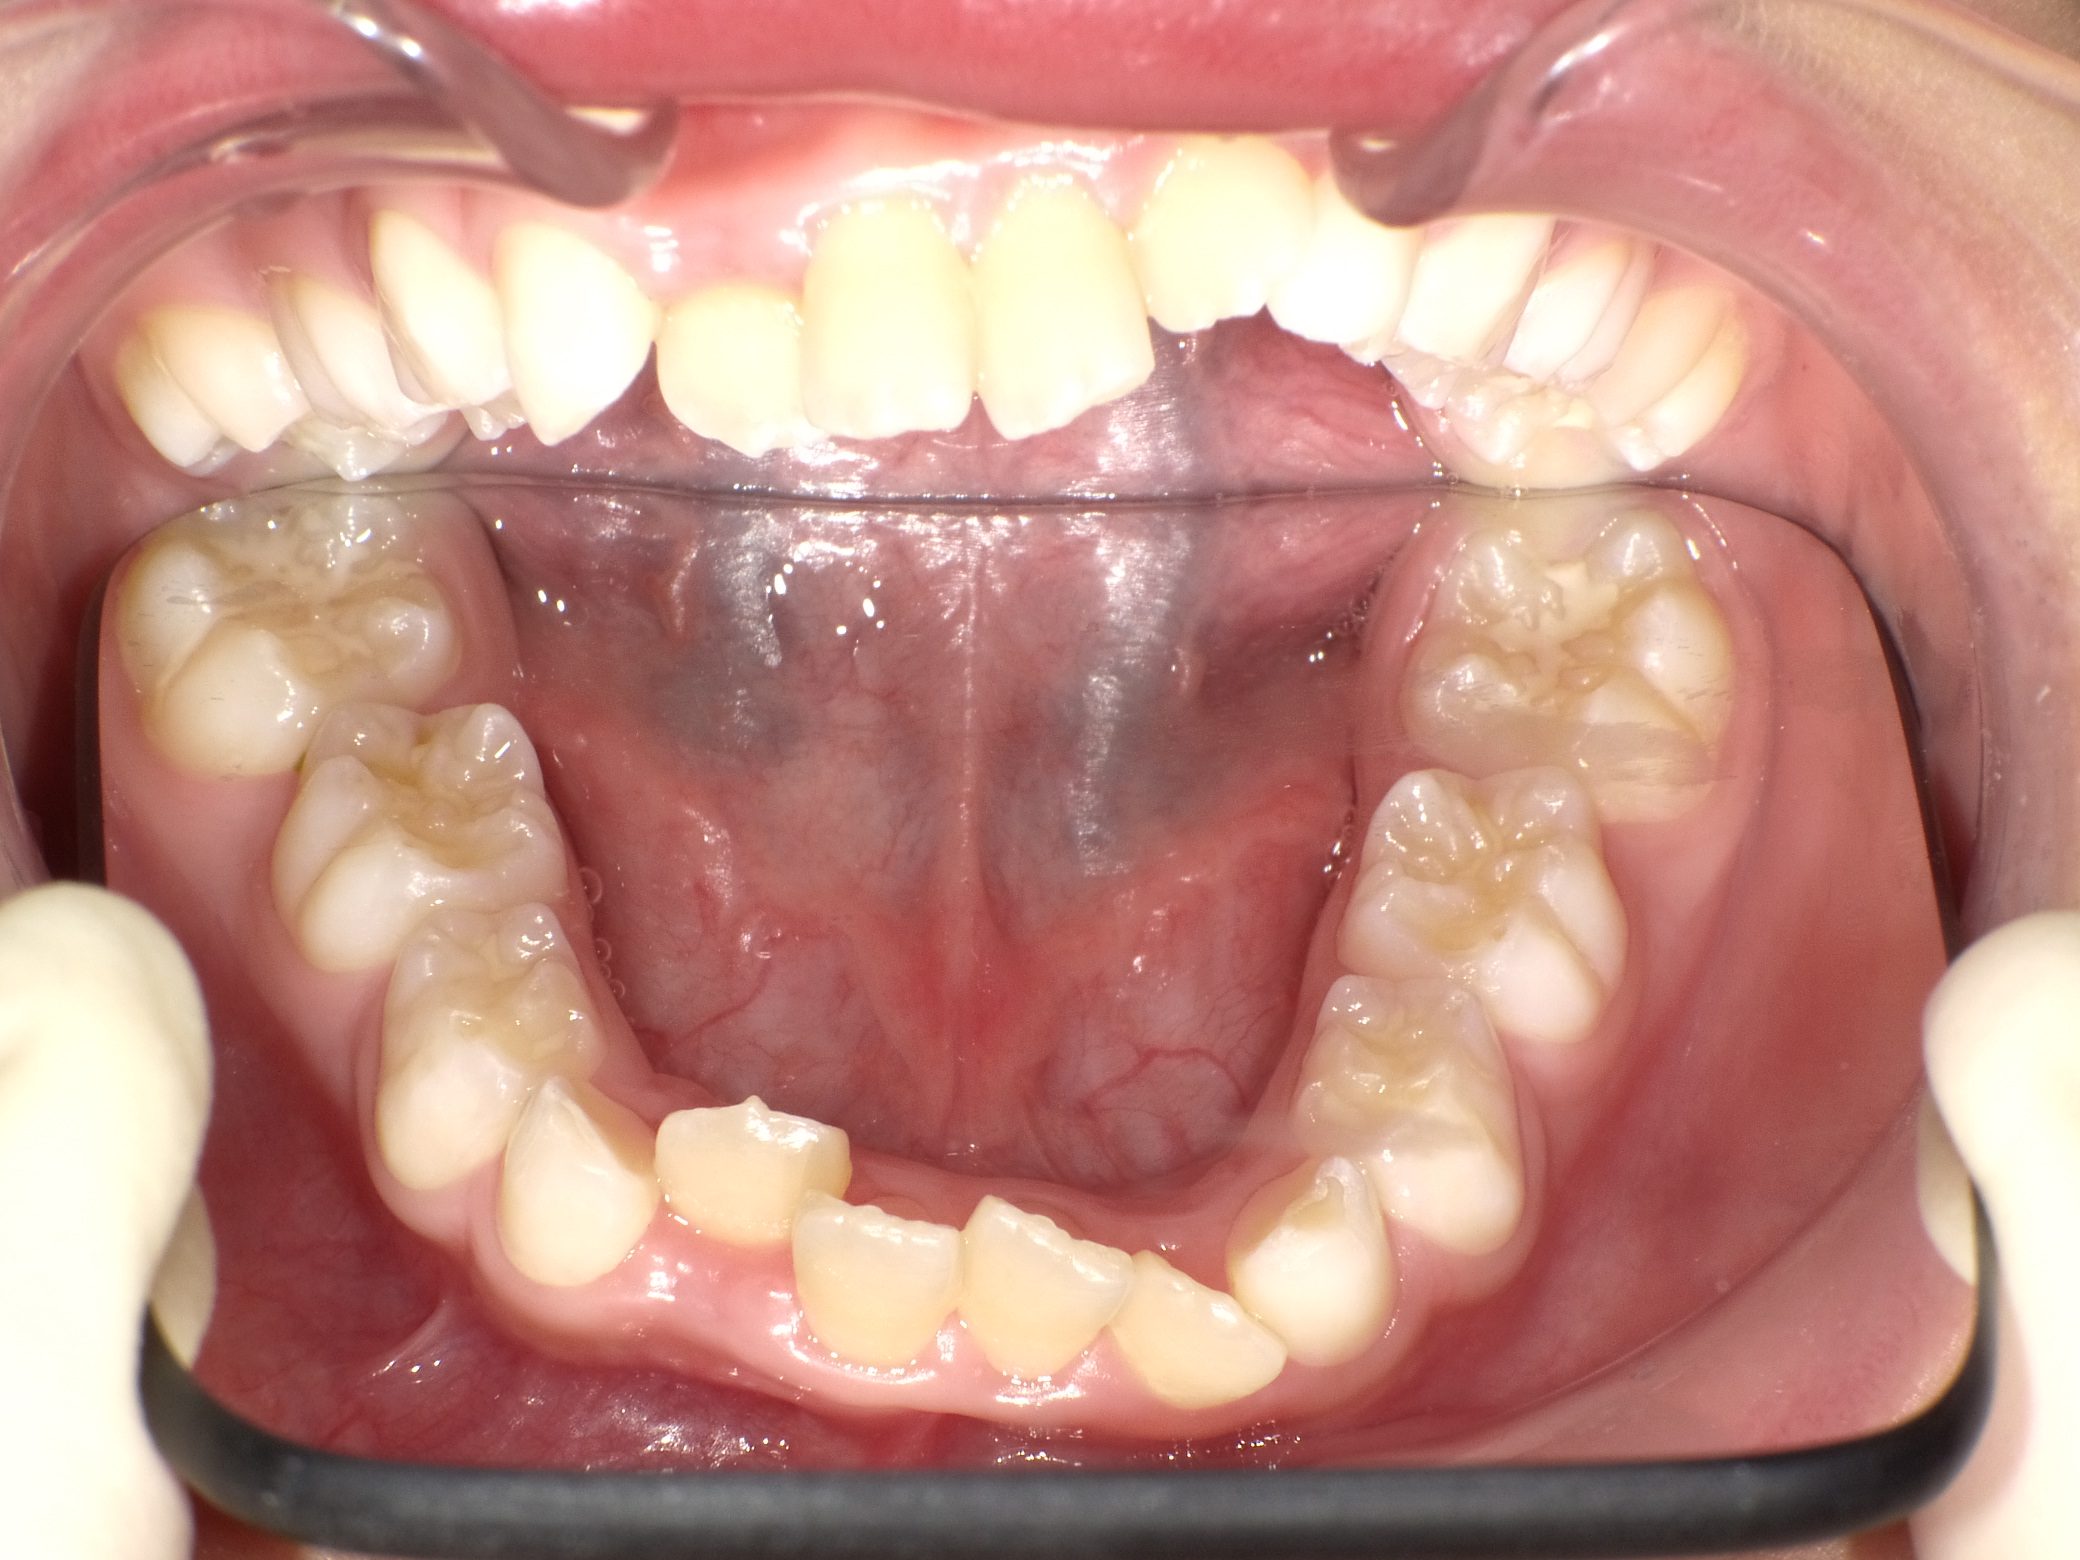

Before

After

【小学生】マイオブレース矯正 上顎前突(出っ歯)と叢生(でこぼこ)を改善

治療期間

2年

治療開始

8歳

種類

マイオブレース矯正

使用装置

機能矯正装置 咬合斜面版

現在は終了後8年たっていますが、今も定期健診にきてくれて 歯並びを保っています